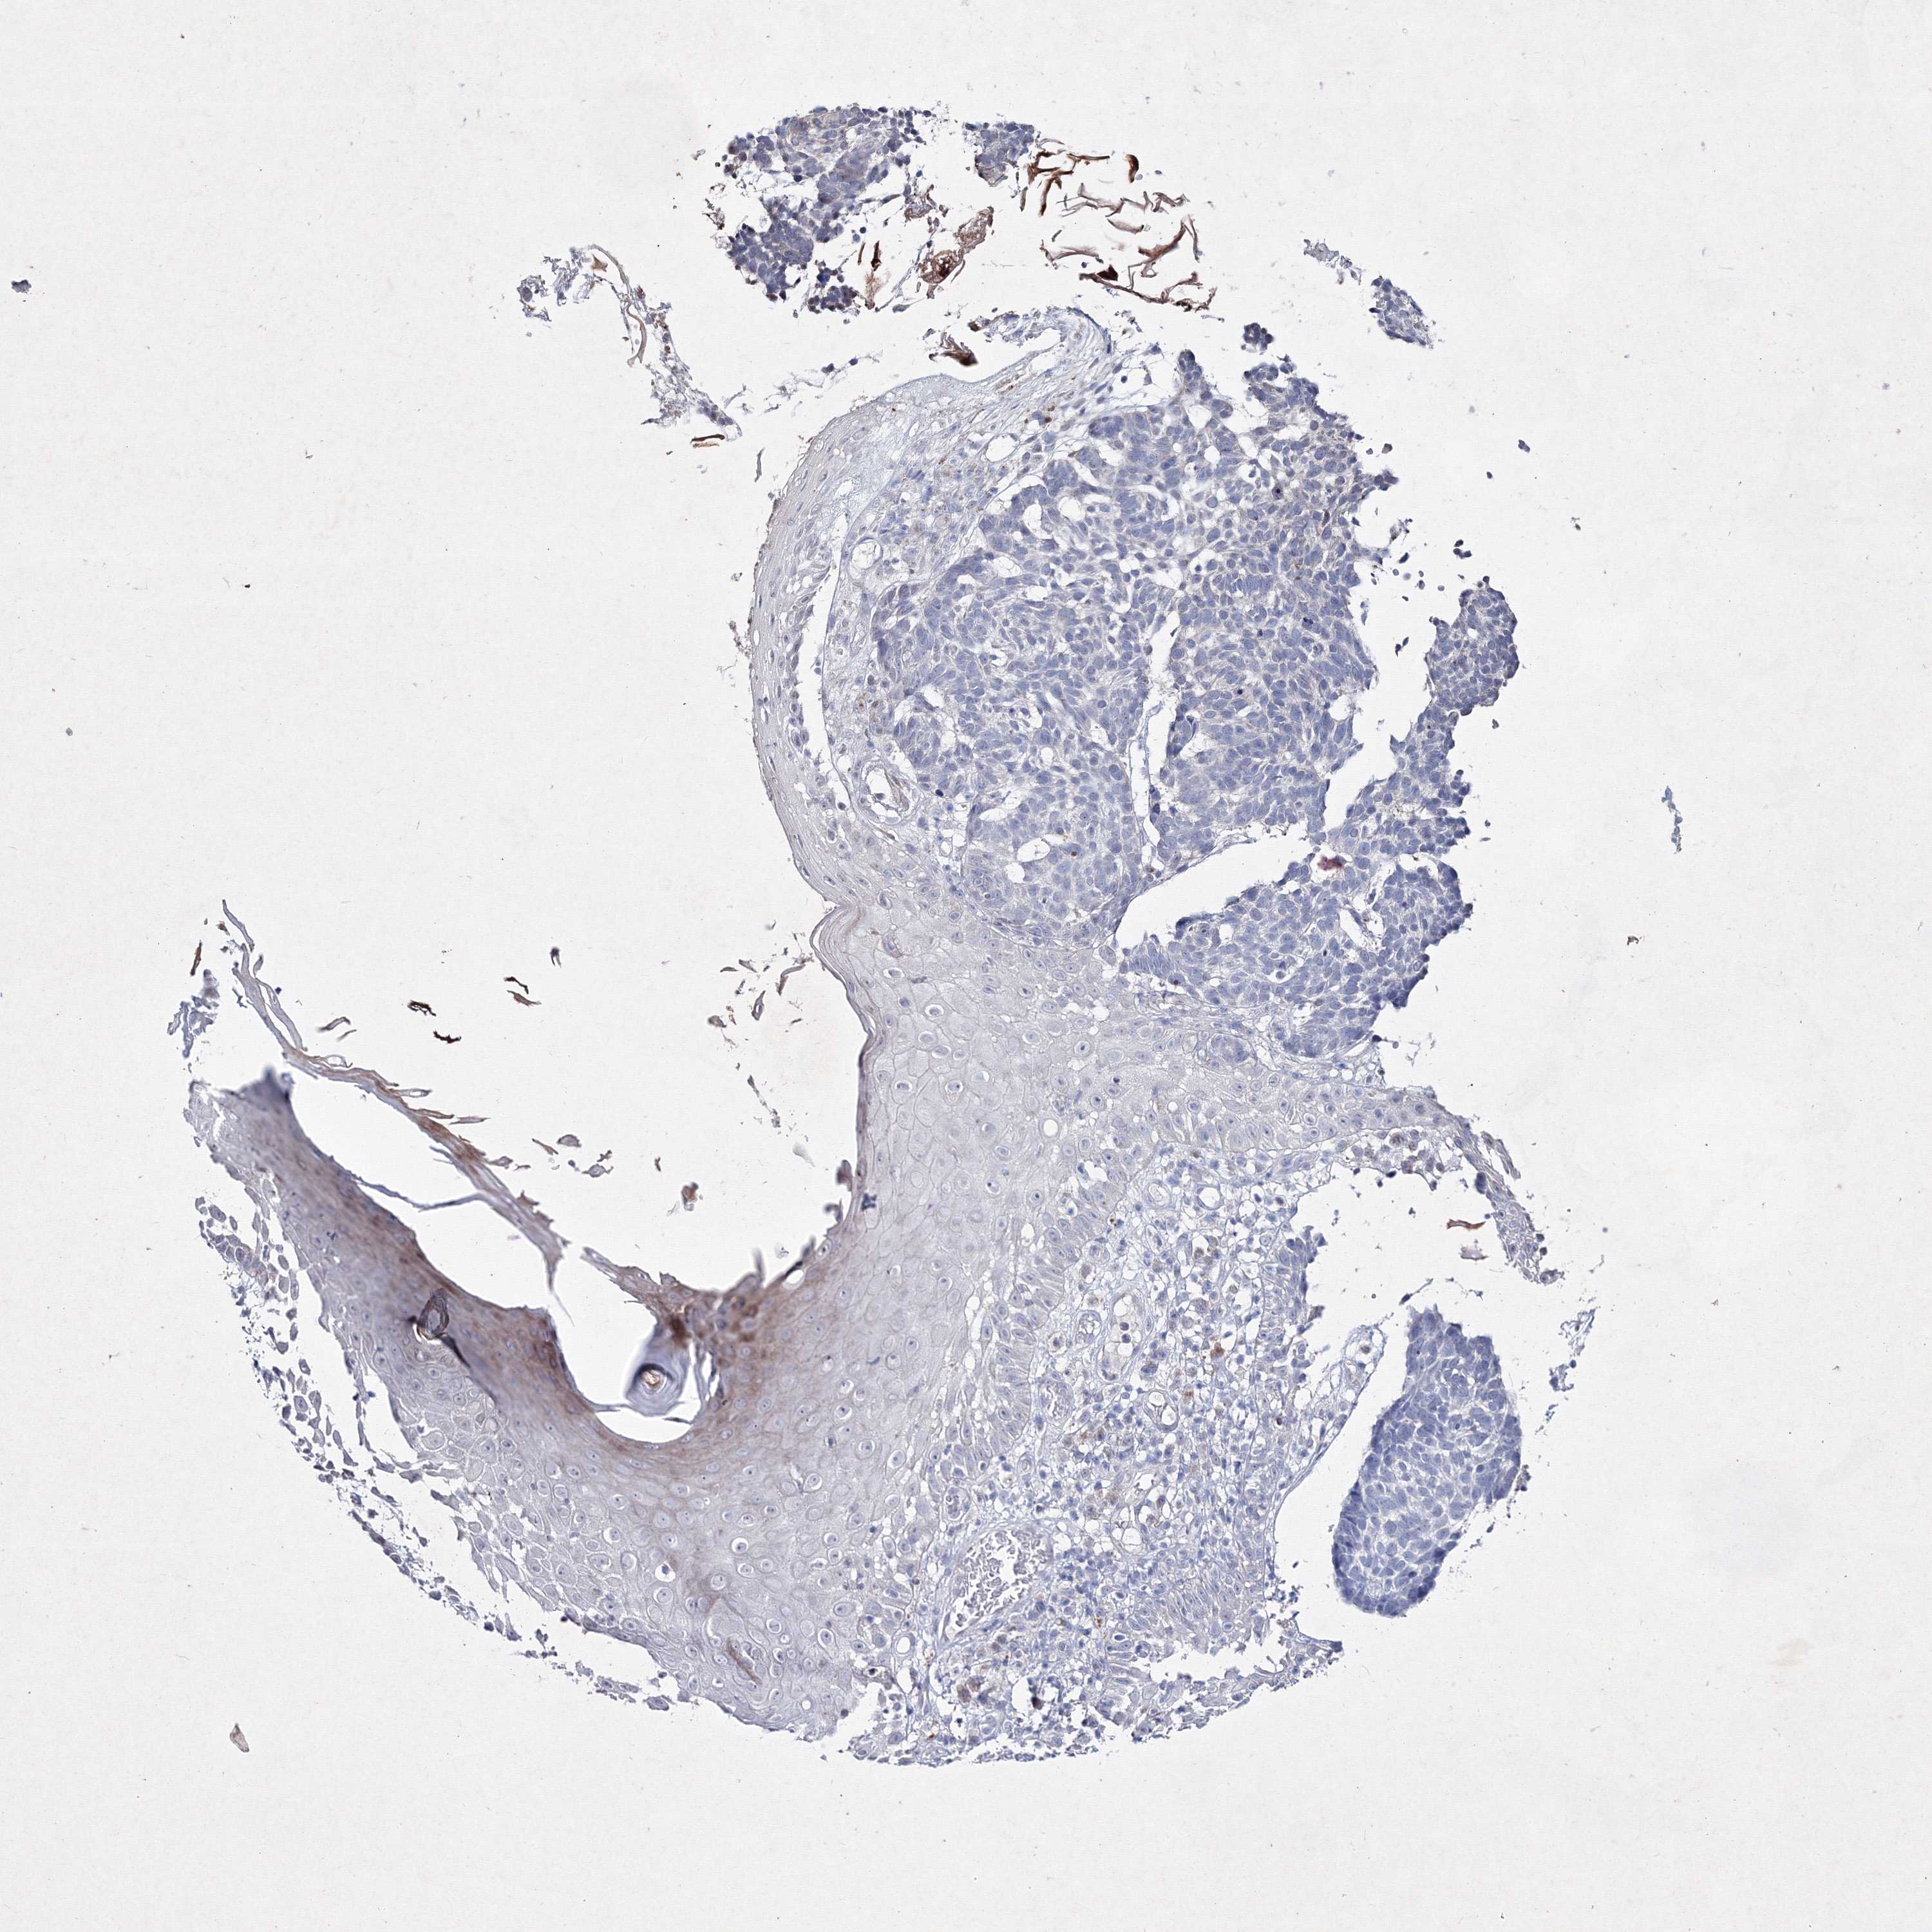

SKIN CANCER - Protein expressioni

A mouse-over function shows sample information and annotation data. Click on an image to view it in a full screen mode. Samples can be filtered based on level of antibody staining by selecting one or several of the following categories: high, medium, low and not detected. The assay and annotation is described here.

Antibody stainingi

Antibody staining in the annotated cell types in the current human tissue is reported as not detected, low, medium, or high, based on conventional immunohistochemistry profiling in selected tissues. This score is based on the combination of the staining intensity and fraction of stained cells.

Each image is clickable and will lead to virtual microscopy that enables deeper exploration of all samples and also displays staining intensity scores, fraction scores and subcellular localization as well as patient and tissue information for each sample.

Antibody HPA037659

Antibody HPA037660

Staining

High

Medium

Low

Not detected

Intensity

Strong

Moderate

Weak

Negative

Quantity

>75%

75%-25%

<25%

None

Location

Nuclear

Cytoplasmic/membranous

Cytoplasmic/membranous,nuclear

Basal cell carcinoma

Squamous cell carcinoma, NOS

Squamous cell carcinoma, metastatic, NOS